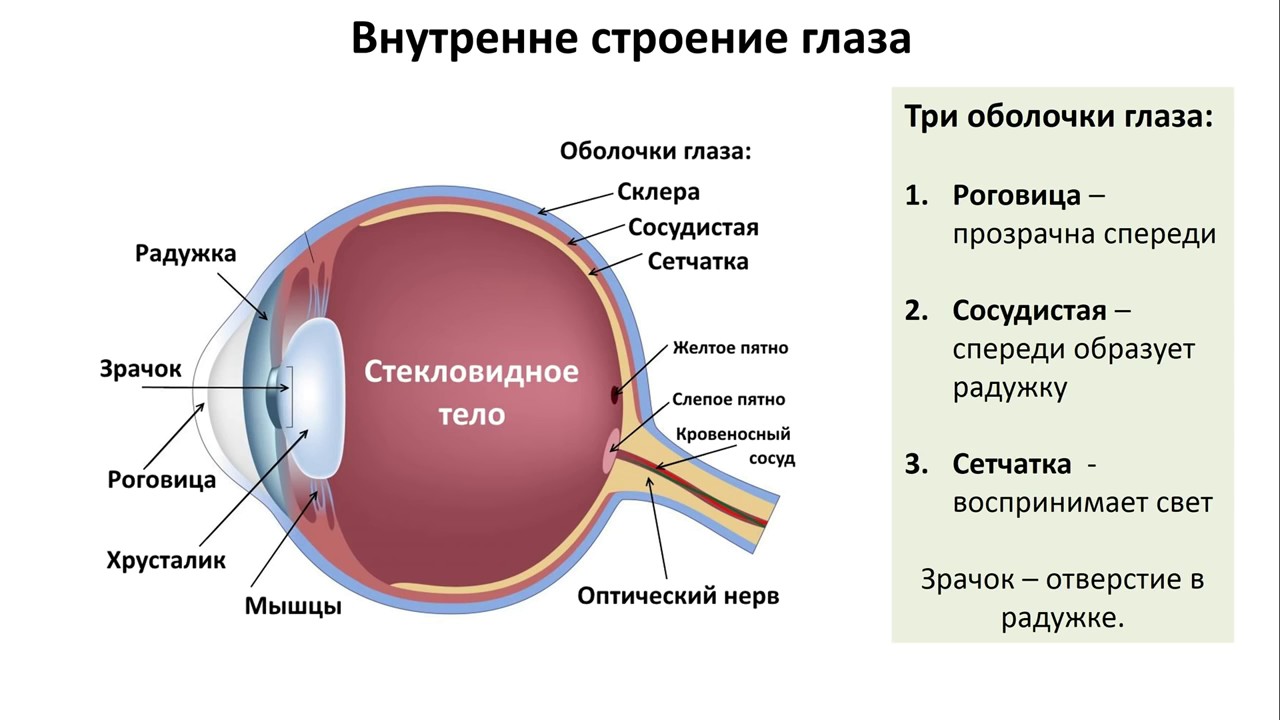

КТ-графики и изображение строения глаза